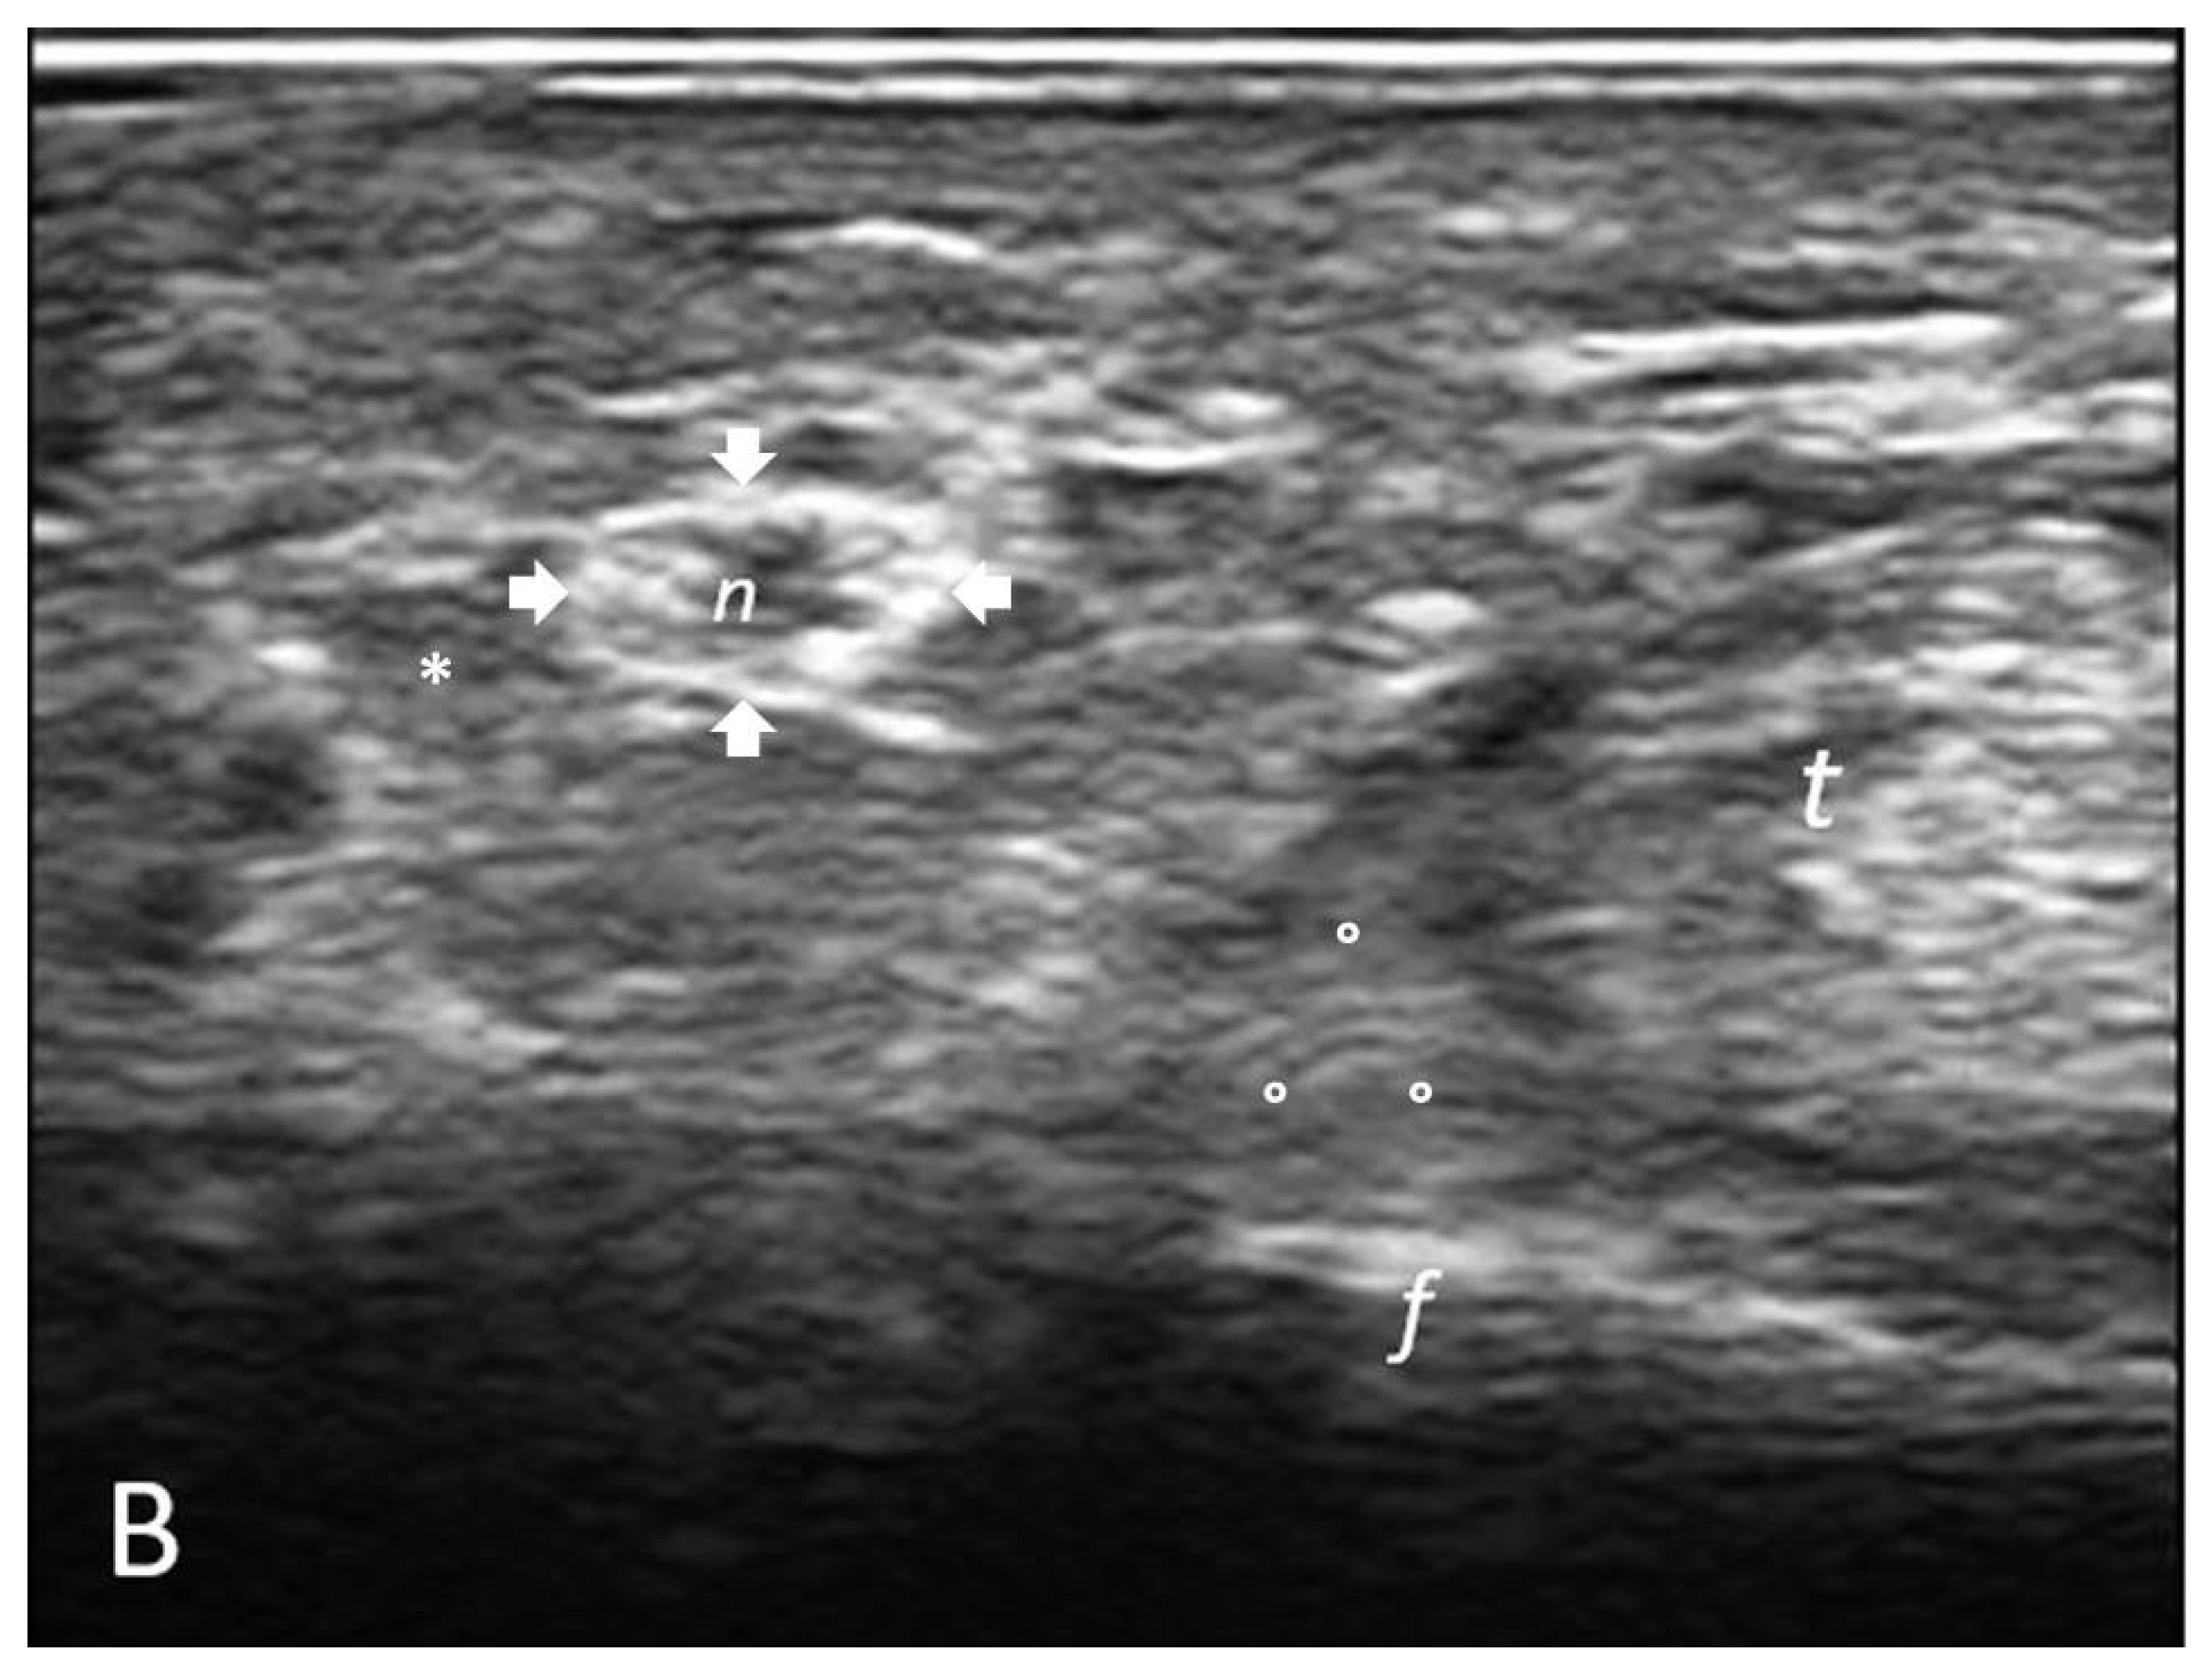

2.3.2. Determination of Cross-Sectional Area (CSA) of Palmar Digital Nerves